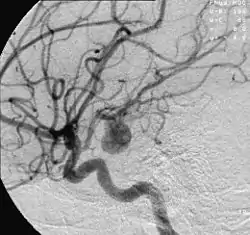

![]() تصوير الأوعية الدموية يُظِهر أم الدم في الشريان الدماغي تصوير الأوعية الدموية يُظِهر أم الدم في الشريان الدماغي | |